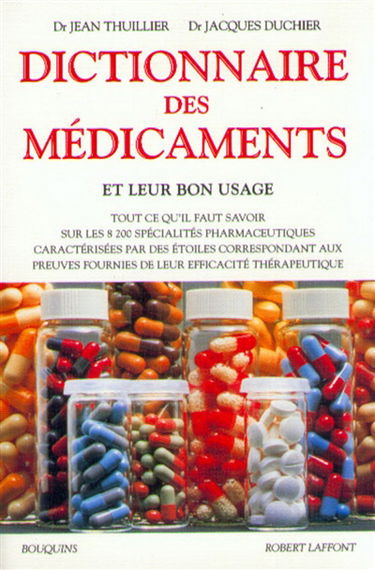

Encyclopédies et dictionnaires thématiques d’occasion

Découvrez tous nos livres d'occasion en ligne dans la catégorie encyclopédies et dictionnaires thématiques. Remplissez votre panier et vos étagères avec de nouvelles lectures passionnantes : faites votre commande parmi des centaines de titres en encyclopédies et dictionnaires thématiques à petit prix sur RecycLivre, avec livraison partout dans le monde ! Des livres de la catégorie encyclopédies et dictionnaires thématiques à donner ? Retrouvez toutes nos solutions de collecte sur cette page. Vous préférez vous faire un peu d'argent et vendre vos livres de seconde main ? Rendez-vous sur notre application de rachat de livres, RecycLivre Rachète ! Lire la suite En voir moins